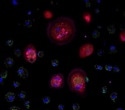

Several techniques, including low-resolution transcriptome profiling via NanoString DSP, spatial transcriptomics via 10x Genomics Visium technology, whole-slide imaging, and single-cell image analysis via the StrataQuest software from TissueGnostics, helped analyze the spatial distribution of IDO1 and PDL1 in the skin tissue of patients with cutaneous leishmaniasis.

Researchers investigated the location and expression of IDO1 and PDL1 within the tissue samples. Multiplexed imaging and transcriptome profiling afforded them useful insights into the distribution of these immune checkpoints within the skin lesions.